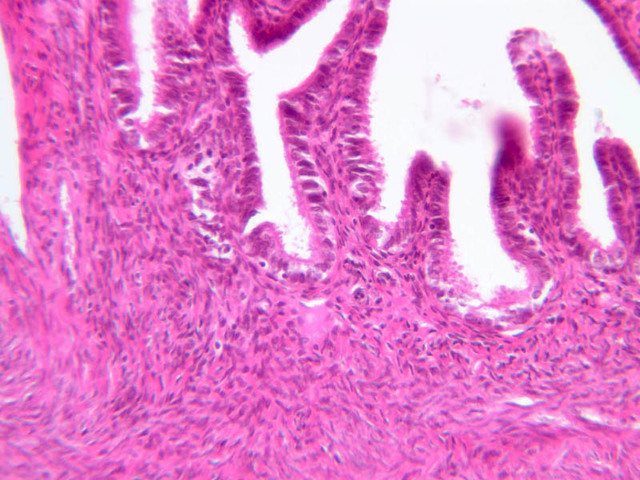

The wall of the uterine tube consists of three layers; a mucosa, a muscularis, and an adventitial/serous coat (B-96 [2.5x, 10x-labeled, 20x, 40x] [2.5x, 10x, 20x, 40x]; B-97, monkey uterus [2.5x, 10x, 20x, 40x]). The mucosa is organized into folds that vary in their degree of complexity with the tube regions. The mucosa is lined by a simple columnar epithelium consisting of two cell types, ciliated and non-ciliated, secretory (B-93 [10x, 20x, 40x-labeled]). The mucosal lamina propria consists of somewhat loose connective tissue and is highly vascular. No muscularis mucosae are present. The muscularis consists of two layers of smooth muscle, the inner being oriented in a circular fashion and the outer longitudinally.

The structure of the uterine tube is under the control of, and responds to, cyclic changes in the levels of steroid hormones. Structural alterations to provide favorable transport for the oocyte commence anew with the beginning of each cycle and peak at mid-cycle just before ovulation. These include increases in height and number of the ciliated cells as well as active secretion in the secretory cell. For the remainder of the cycle thereafter, dedifferentiation occurs. The cyclic changes occur to a greater extent in the upper ampulla and infundibulum. The margin of the infundibulum is drawn out into numerous finger-like processes called fimbrae. Microscopic examination of these will reveal that within the lamina propria are numerous large blood vessels, especially veins, as well as bundles of smooth muscle forming an intervening network. At the time of ovulation, the vessels become enlarged with blood, causing turgidity, which when combined with smooth muscle contraction brings the infundibular opening into close apposition with the ovarian surface.